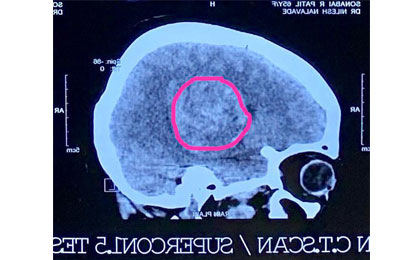

Brain Tumor Surgery  14/02/2019

cricket ball size tumor removed

Huge Haemangioma PRE

• Huge Haemangioma PRE